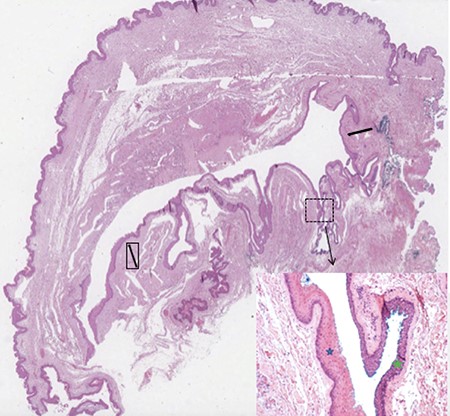

Microscopic overview of the surgical specimen showing a large hybrid epidermal inclusion cyst (black arrows) lined by squamous epithelium (blue star) with areas of transitional epithelium (green star; haematoxylin and eosin stains).